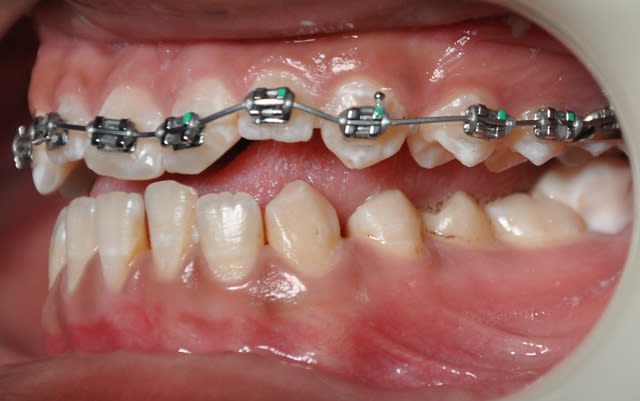

voici la première étape